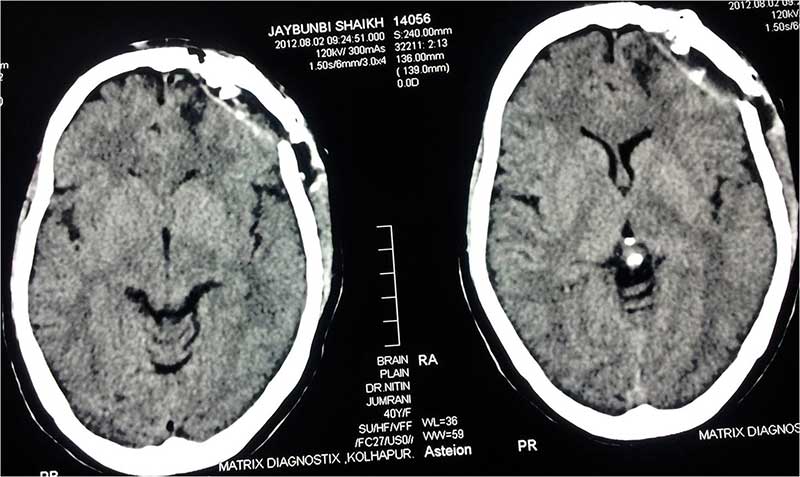

Post Op 1 CT Scan